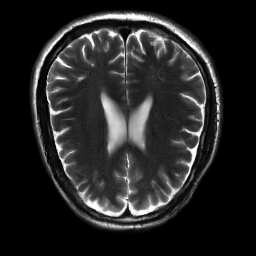

Generative adversarial networks are a kind of deep generative model with the potential to revolutionize biomedical imaging. This is because GANs have a learned capacity to draw whole-image variates from a lower-dimensional representation of an unknown, high-dimensional distribution that fully describes the input training images. The overarching problem with GANs in clinical applications is that there is not adequate or automatic means of assessing the diagnostic quality of images generated by GANs. In this work, we demonstrate several tests of the statistical accuracy of images output by two popular GAN architectures. We designed several stochastic object models (SOMs) of distinct features that can be recovered after generation by a trained GAN. Several of these features are high-order, algorithmic pixel-arrangement rules which are not readily expressed in covariance matrices. We designed and validated statistical classifiers to detect the known arrangement rules. We then tested the rates at which the different GANs correctly reproduced the rules under a variety of training scenarios and degrees of feature-class similarity. We found that ensembles of generated images can appear accurate visually, and correspond to low Frechet Inception Distance scores (FID), while not exhibiting the known spatial arrangements. Furthermore, GANs trained on a spectrum of distinct spatial orders did not respect the given prevalence of those orders in the training data. The main conclusion is that while low-order ensemble statistics are largely correct, there are numerous quantifiable errors per image that plausibly can affect subsequent use of the GAN-generated images.